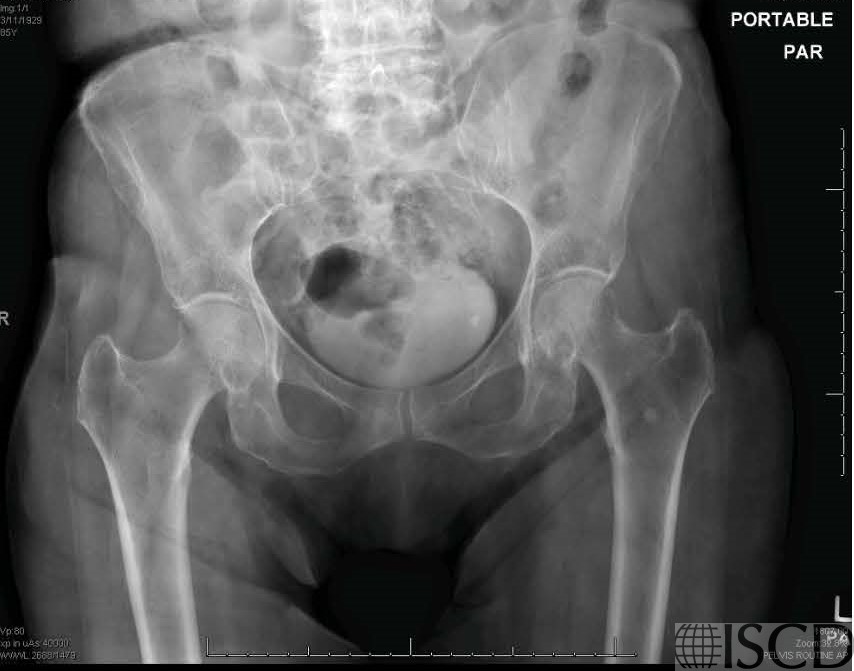

The accompanying radiograph also shows the bone island.

There is a bone island seen on the left Hologic proximal femur scan. On the accompanying pelvic radiograph, the sclerotic foci in the left ilium and proximal femur were read as consistent with bone islands. A bone island is also known as an enostosis and is a benign lesion. Most lesions are small and round and are composed of cortical bone within the cancellous bone.